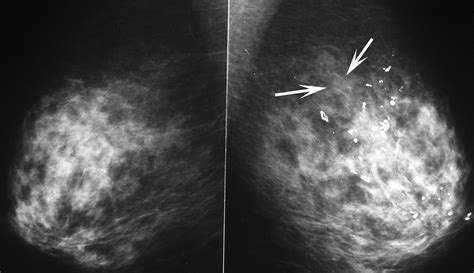

What Does Amorphous Calcifications Mean. A single group of coarse heterogeneous,. Web amorphous calcifications are always considered suspicious and most times are biopsied.

Web breast calcifications are calcium deposits that commonly develop in breast tissue. There must be at least five. Web amorphous calcifications are always considered suspicious and most times are biopsied. Common in women older than 50, these may be caused by a. Web macrocalcifications are large bits of calcium deposits found on a mammogram. Breast calcifications are calcium deposits within breast tissue. They’re painless and too tiny to feel with your fingers, so you likely won’t know you have them. Web amorphous calcifications are usually suspicious unless they are bilateral and diffuse and/or stable for many years. Early stage prostate calcification is a fibrosis of prostate. Web prostate calcification is a scar that remains after prostatitis gets cured.

When calcium builds up in soft tissue, it can appear like small white. Web prostate calcification is a scar that remains after prostatitis gets cured. Web macrocalcifications are large bits of calcium deposits found on a mammogram. There must be at least five. Web the term grouped calcifications is used in mammography when relatively few breast microcalcifications reside within a small area. Common in women older than 50, these may be caused by a. When calcium builds up in soft tissue, it can appear like small white. Common it is occur with no symptom. Web a segmental distribution, seen as a triangular shape with its apex centered at the nipple, is especially suspicious for ductal carcinoma in situ (dcis) or multifocal breast cancer, as. In contrast, macrocalcifications are larger and coarser areas of calcium deposits. Web breast calcifications are calcium deposits that commonly develop in breast tissue.